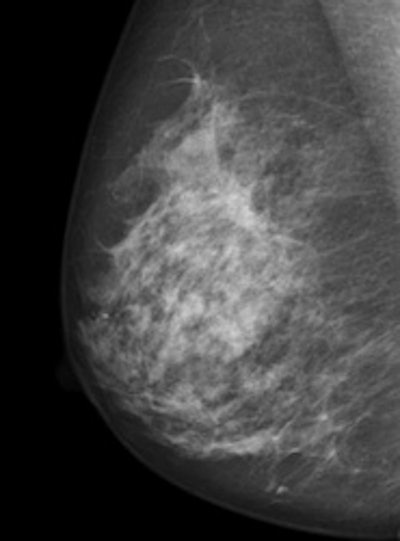

The value of annual mammography screening remains controversial, but for the most part radiologists agree on its utility. With the development of full-field digital mammography, even more cancers are detected, especially in women with dense breasts. The major drawback, however, is "the difficulty of finding and discerning a subtle change against the complex background of the glandular tissue, a particular issue for younger premenopausal women with a so-called dense glandular background pattern," wrote Dr. Matthew Wallis, a consultant radiologist and the director of the Cambridge and Huntingdon Breast Screening Service in the U.K. (Radiol, 24 January 2012, online first).

With tomosynthesis, low-dose images are obtained over a limited arc, and the projections are mathematically reconstructed into a series of sections with the hope that specificity and sensitivity will be improved. Initial work using tomosynthesis as an add-on to conventional 2D mammography suggested the potential for substantial improvements in specificity, the authors noted. They compared the diagnostic accuracy of 2D digital mammography with that of two-view (mediolateral and craniocaudal) and single-view (mediolateral oblique) tomosynthesis in an observer study involving two institutions: Cambridge and Capio St Göran's Hospital in Stockholm.

Ten accredited readers classified 130 women with breast density of 2 to 4 using 2D mammography and two-view tomosynthesis. Another 10 reviewed the same cases using 2D mammography but with single-view tomosynthesis.